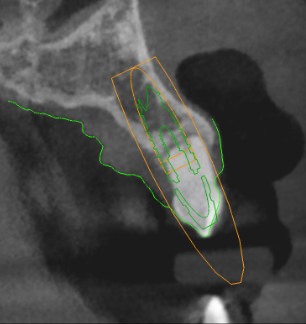

Step 3 — Prosthetic-driven implant planning. This is the key step. The CS 3D Imaging Prosthetic-Driven Implant Planning module automatically merged the CBCT volume with the intraoral scan — aligning hard tissue (bone) with soft tissue (gingiva and teeth) in a single view. The implant was then positioned using a crown-down approach: the ideal restoration position determined the implant axis, not the other way around.

CS 3D Imaging automatically merging CBCT and intraoral scan data for prosthetic-driven planning Implant position planned using crown-down approach in CS 3D Imaging

Step 3 The Prosthetic-Driven Implant Planning module in CS 3D Imaging software automatically merges the CBCT and intraoral scan. The implant is positioned based on the ideal crown position — not just the available bone.

Prosthetic-driven planning puts the crown first. The implant position was determined by where the final restoration needed to be — not by where the bone happened to be easiest to drill. CS 3D Imaging's Prosthetic-Driven Planning module merges your CBCT and intraoral scan automatically, so you plan from the crown down in a single software environment.